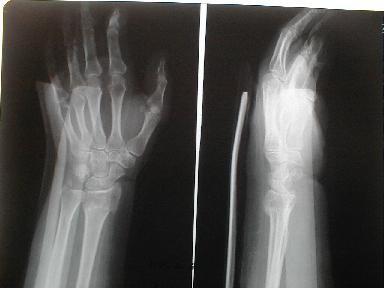

2月4日受傷

とう骨下端 尺骨茎状突起骨折

皮下溢血、腫脹著明で運動制限有り

2月6日 整復後固定 |